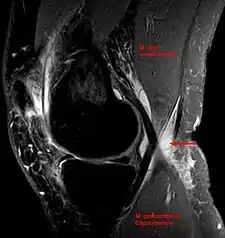

Baker's cyst on axial MRI with communicating channel between the semimembranosus muscle and the medial head of the gastrocnemius muscle.

Baker's cyst on MRI, sagittal image